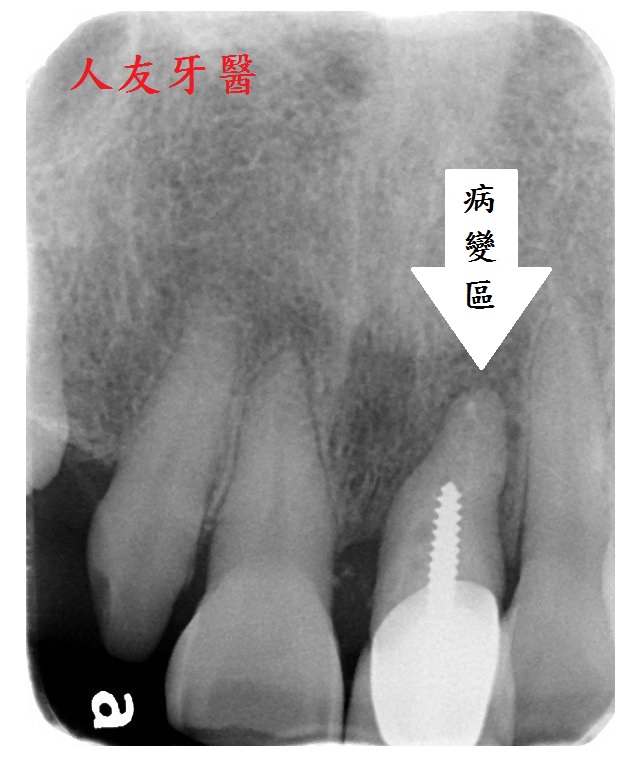

患者多年前左上正門牙因蛀牙在他院做根管治療並加裝柱心及金屬瓷牙作為膺復假牙,幾年後引發牙根囊腫,因化膿感到不適尋求本院診治

經過醫師專業評估,由於蛀牙過深,拆除牙冠後原本的牙齒所剩過薄,已無重新根管治療的條件,建議拔除後再進行微創植牙手術

想詢問周醫師如何處理。醫師看了X-RAY發現右邊側門牙紅色圓圈的地方有病變,有可能留不住。左邊側門牙藍色箭頭牙齒有裂到肉,也可能留不住。經過討論後建議都拔除。